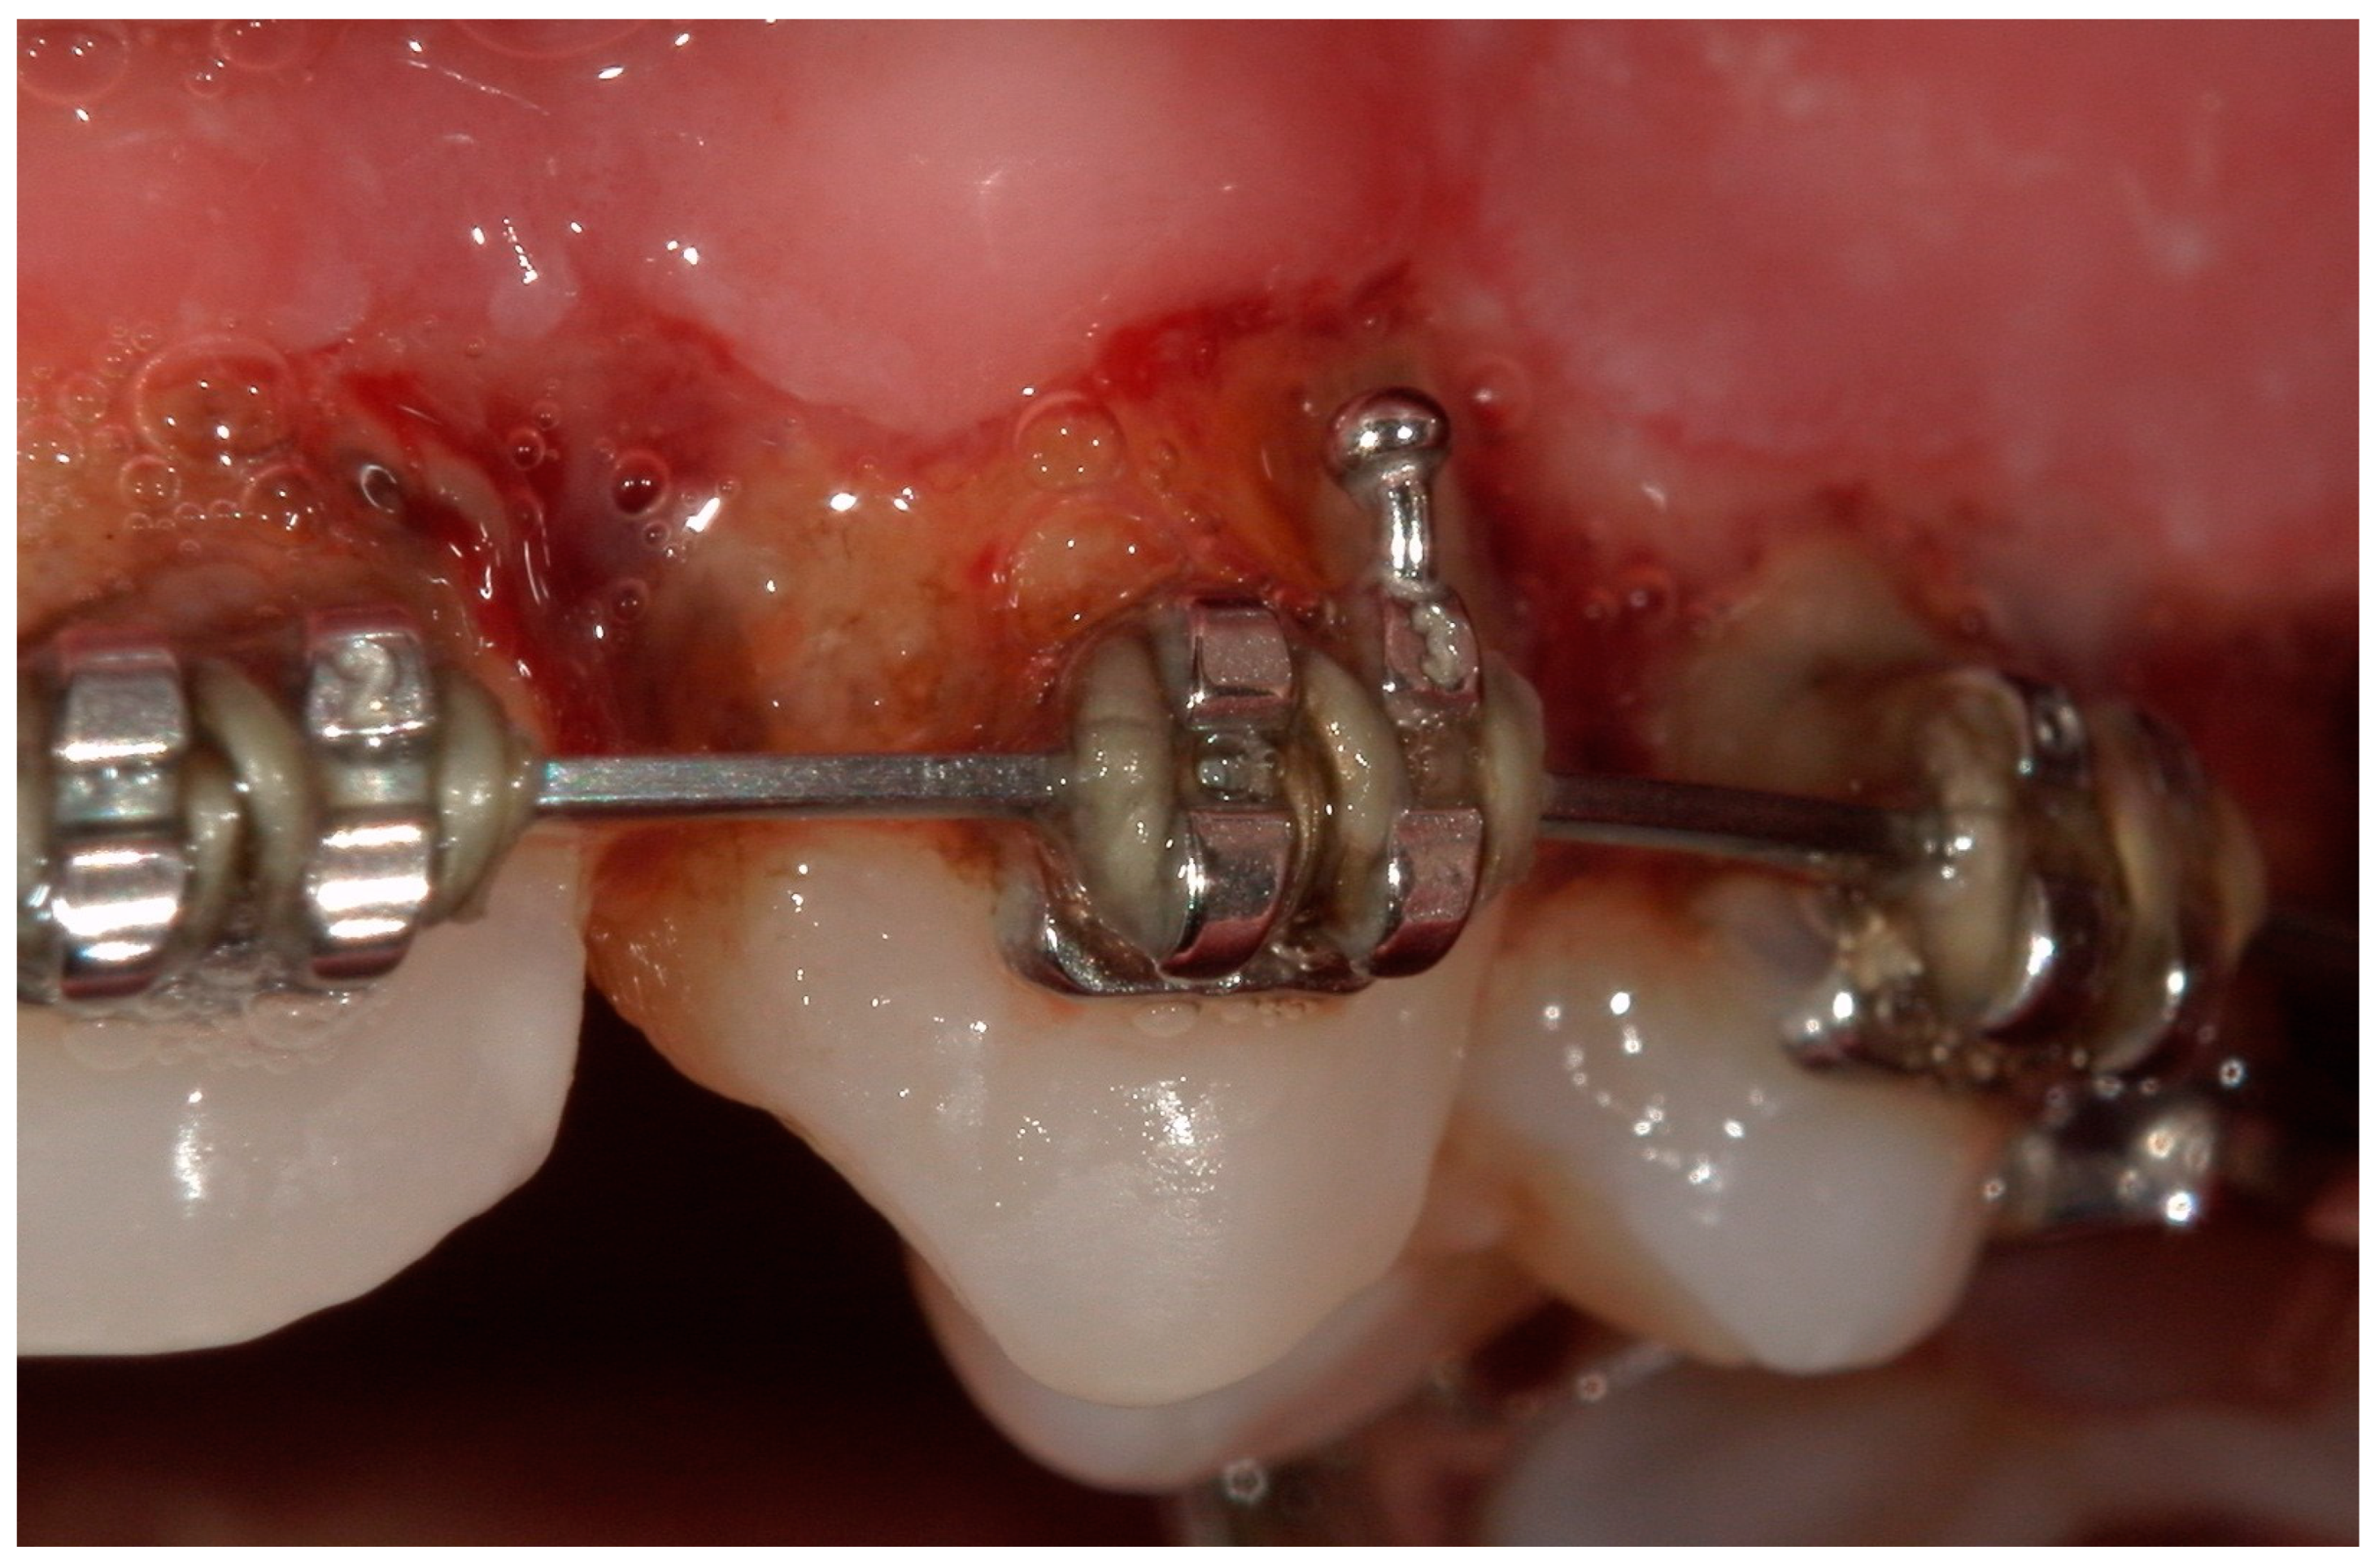

4.1. Case 1

4.2. Case 2